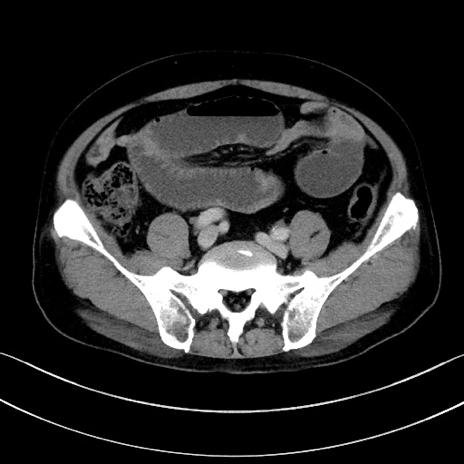

症例15(横断像)

【症例】70歳代男性

【主訴】腹痛

【現病歴】今朝から腹痛あり。全体的に痛い。特に左上の方。排ガスが今日はない。冷や汗が出る。

【既往歴】直腸癌術後

【身体所見】左側腹部〜上腹部に圧痛あり。腹膜刺激症状明らかなではない。軽度反跳痛。左下腹部に術後瘢痕あり。

【データ】WBC 7700、CRP 0.02